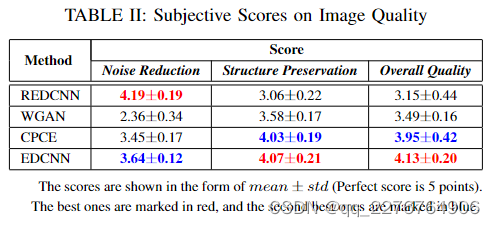

本小节显示了我们模型的降噪结果。 为了公平起见,我们选择REDCNN[9]、WGAN[11]和CPCE[14]进行比较,因为他们的单一模型的设计与我们提出的模型相同。 这些模型也采用了卷积神经网络的结构,但各有其特点。 我们重新实现这些模型,在相同的训练集上训练它们。 表的左侧部分。 我展示了他们使用的损失函数的配置,也包括我们的模型。

在降噪任务中,定量分析模型有三个常用标准,包括峰值信噪比(PSNR)、结构相似度(SSIM)和均方根误差(RMSE)。 此外,我们添加了一个度量VGG-P,它是基于VGGNet19[22]的常用感知损失,测量最终卷积层特征空间中的距离[21]。 如表右半部分所示。 I,所有模型都在 AAPM 挑战赛数据集的分割测试集上进行测试。 我们计算并计算这些指标的平均值和标准差。 通过该表,我们可以发现基于MSE损失的REDCNN在PSNR和RMSE指标上具有最好的性能。 通过使用基于VGGNet的感知损失,WGAN和CPCE在VGG-P上有很好的结果。 至于我们提出的 EDCNN,基于复合损失,它在每个标准上都达到了最佳或次优的结果,这可以平衡每像素和结构性能。

为了获得定量的视觉评价,我们进行了盲人阅读研究。 具体来说,我们在测试集中选择了20组模型不同身体部位的去噪结果。 每组包括六幅 CT 图像。 以LDCT和NDCT图像作为参考,其他四张图像是上述四个模型的输出,在每组中随机打乱。 要求读者对降噪后的CT图像进行降噪、结构保存和整体质量三个级别的评分,每项满分为5分。 如表所示。 II,我们以平均值±标准差的形式呈现主观得分的统计数据。 REDCNN 的降噪性能最好,基于 GAN 的 WGAN 和 CPCE 在结构保留方面得分很高。 关于我们设计的 EDCNN 模型,由于复合损失,它同时考虑了降噪和结构保留。 此外,EDCNN 在整体图像质量方面获得了高分。